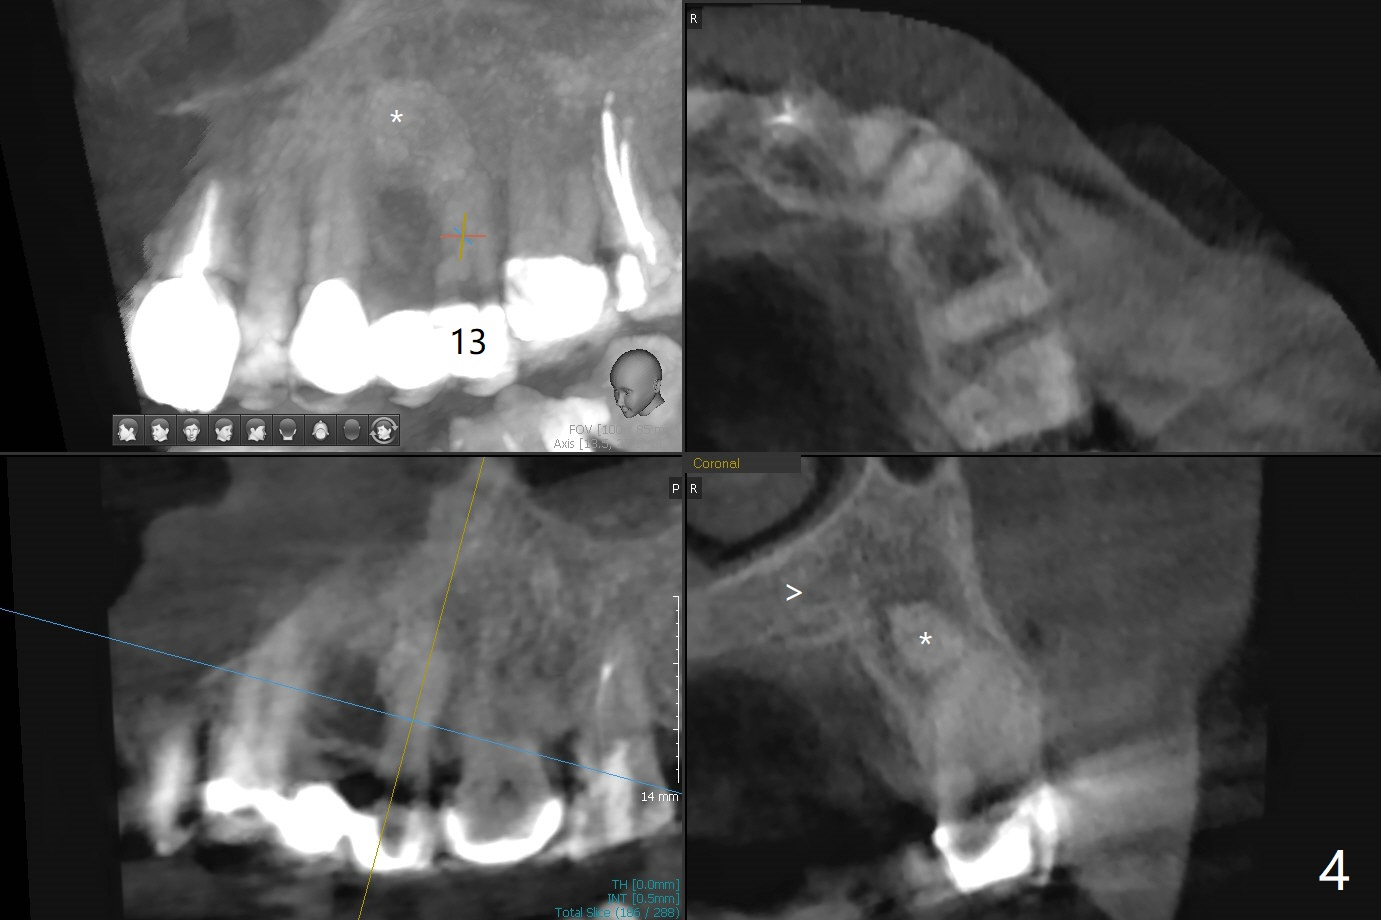

A 73-year-old woman has had discomfort with the upper left FPD for long time (Fig.1). A large asymptomatic fistula is found recently above the pontic with a small superior pedicle (Fig.2,3 <). CT shows radiopaque (Fig.1,4 *) and radiolucent (Fig.4 >) lesions are associated with the tooth #13, instead of the tooth #11.